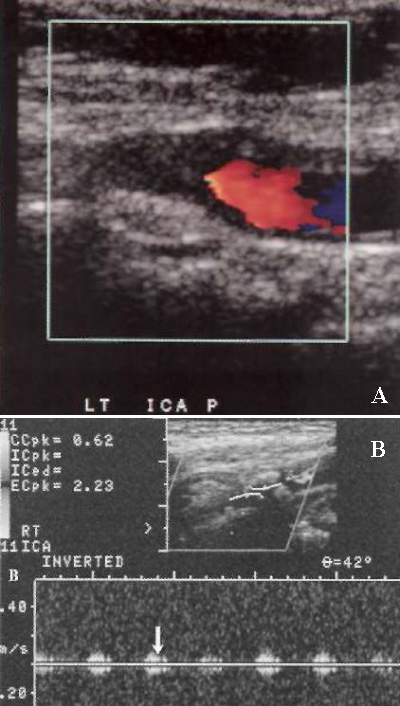

Окклюзию внутренней сонной артерии следует подозревать в случае отсутствия артериальной пульсации, наличия эхогенного материала, который заполняет просвет сосуда, отсутствия кровотока на цветовой и спектральной допплерографии, а также при небольших размерах сосудов, которые наблюдают при хронической окклюзии. В случае окклюзии внутренней сонной артерии кровоток по общей и наружной сонным артериям не нарушается, в дистальном отделе общей сонной артерии может обнаруживаться пристеночный удар – сигнал невысокой скорости, который образуется при ударе крови об атеросклеротическую бляшку (фото 11).

Фото 11. Окклюзия внутренней сонной артерии. А – на цветовой допплерограмме наблюдается отсутствие кровотока и отсутствие артериальной пульсации. В – стрелкой обозначен пристеночный удар – приглушенный сигнал низкой скорости, который образуется при ударе крови о тромб или бляшку, закупоривающую сосуд